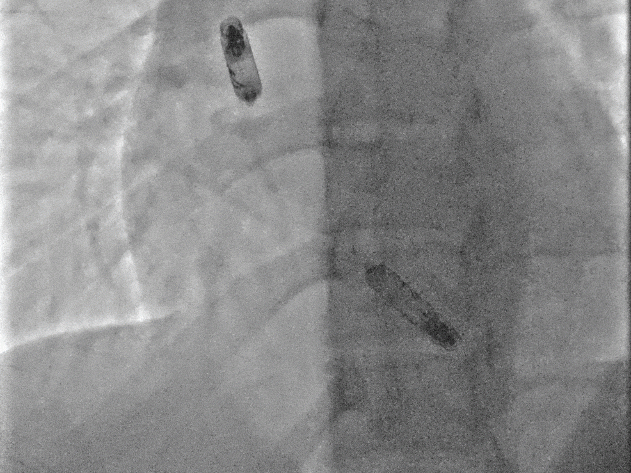

以上两位患者均以标准流程成功植入Aveir™ DR,最终固定位置影像:

病例1 RAO

病例1 LAO